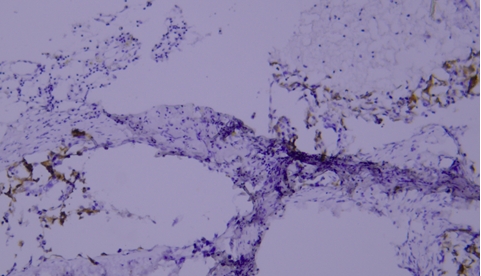

CD45 staining of paraffin-embedded human lymph node sections: Due to insufficient tissue fixation, lymphocytes at the edge of the lymph node show strong CD45 positivity, while those in the inner part of the tissue exhibit weak positivity, leading to uneven staining overall.